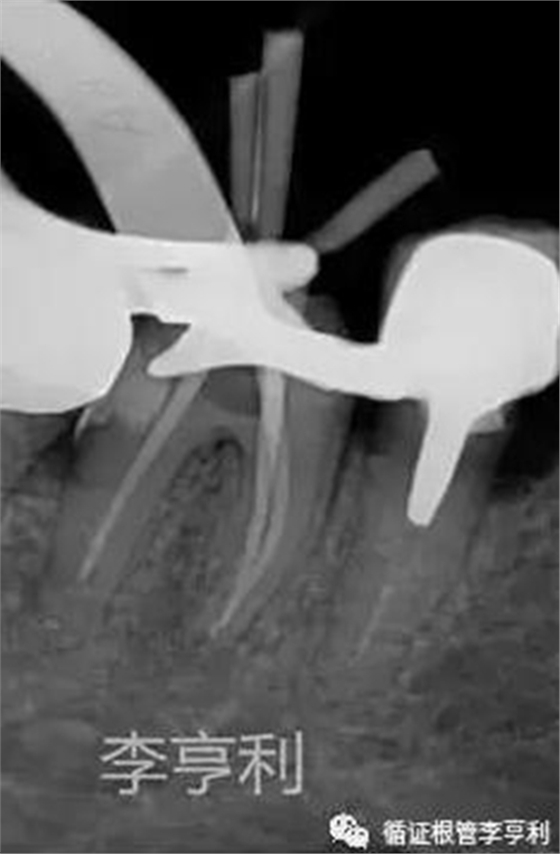

暴露器械斷端 (2017-06-26)

器械被超聲震出 (2017-06-26)

分離器械約為4mm長 (2017-06-26)

治療過程:由于患者根管系統(tǒng)較細(xì)窄,無法建立旁路疏通MB根,因此決定取出分離的器械。首先在顯微鏡下暴露器械斷端,然后使用超聲工作尖震動斷針,30分鐘內(nèi)斷針被順利震出,然后疏通MB到根尖。之后就常規(guī)完成剩余根管治療步驟,轉(zhuǎn)回進(jìn)行后續(xù)冠修復(fù)。

超聲震蕩方法的優(yōu)勢在于效率最高,且無需特殊的器械設(shè)備。一般用于斷械長度在4.5mm以內(nèi),其所需時間一般為60min以內(nèi),否則取出的可能性會隨著時間遞增而迅速下降;

注意保護(hù)其余根管口,避免取出斷針時掉落于其他的根管內(nèi);

使用超聲工作尖的時候,一定要注意保護(hù)根管壁,避免發(fā)生側(cè)穿或過度削弱牙根抗力;